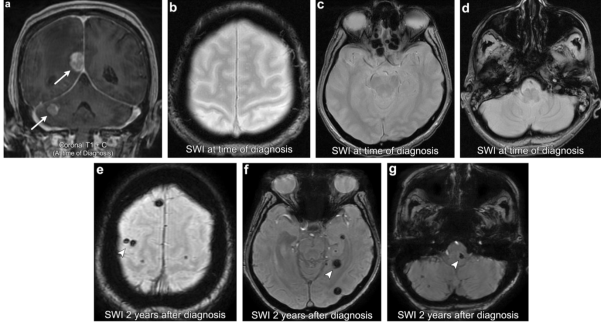

案例2:转移瘤放疗后诱发海绵状血管瘤

76 岁女性,有肺癌病史,出现多发性颅内转移瘤(箭头)。诊断SWI显示无局灶性异常T2星状低信号/在脑实质内的开花样变。在接受全脑放疗(WBRT)2年后,进行SWI成像显示多处新的异常局灶性T2星状低信号分散在脑实质内(箭头所指),与放射诱发的海绵状血管瘤一致。